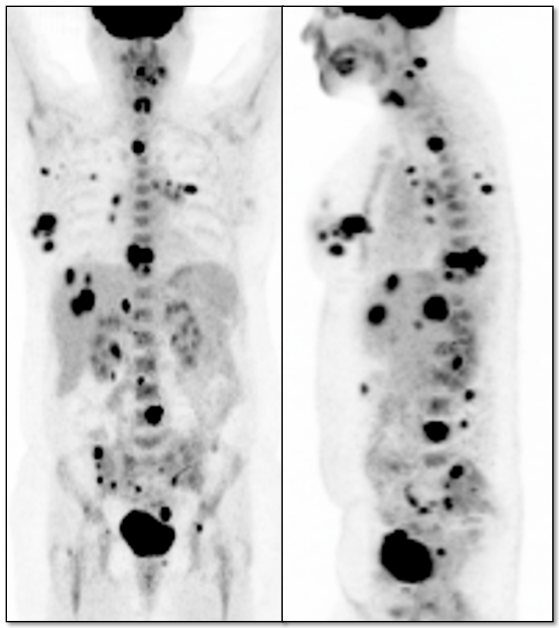

- Assess Response to Therapy